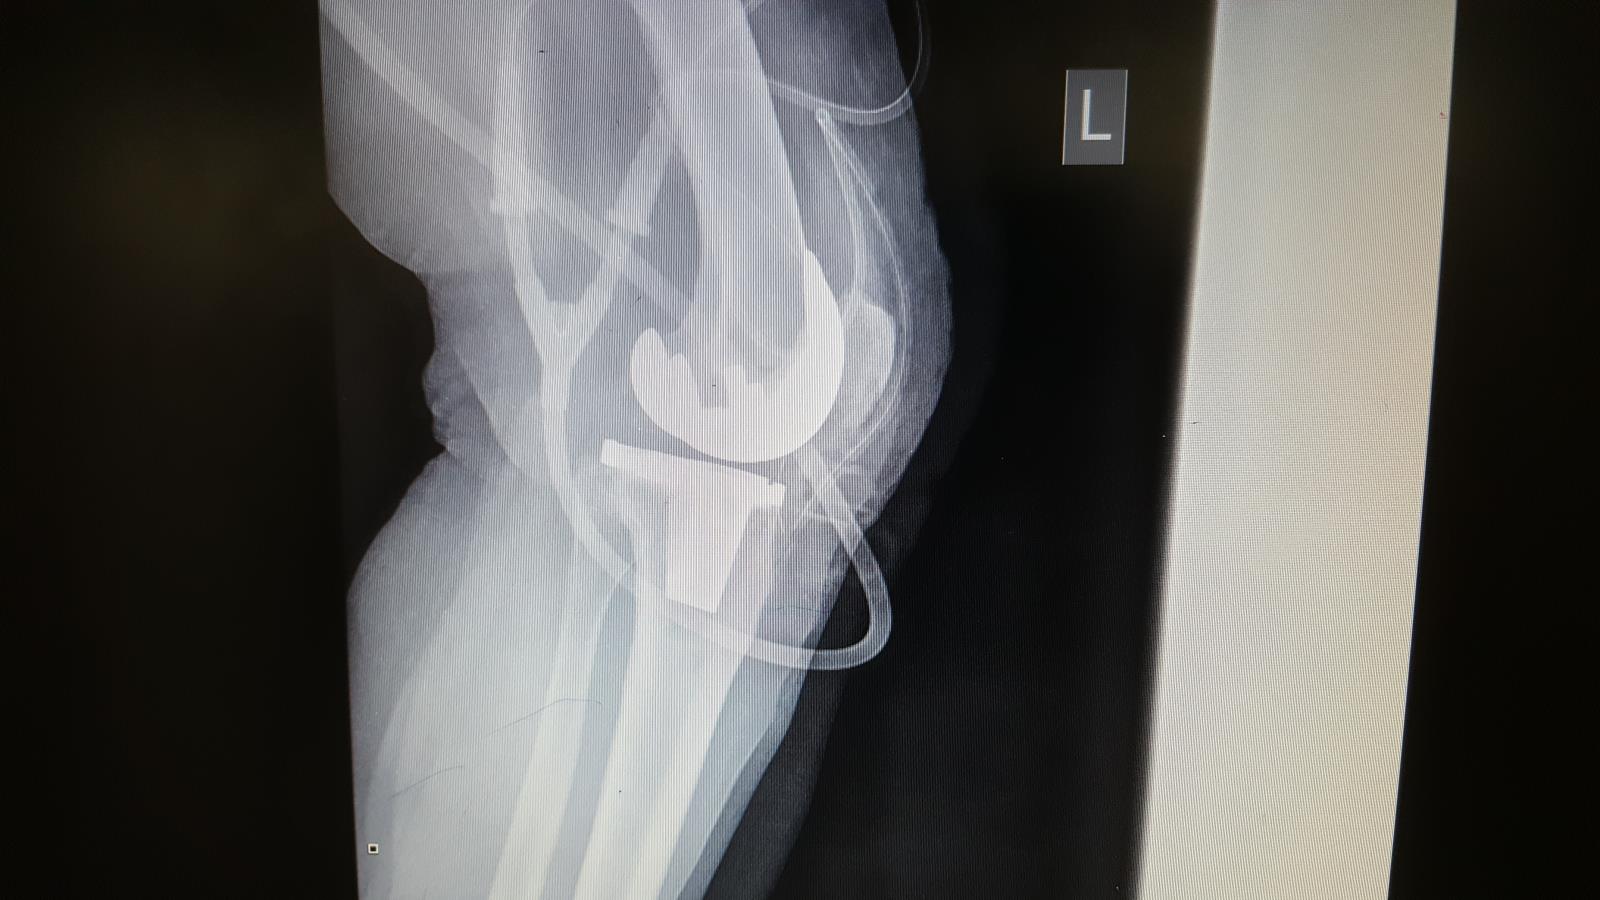

Rentgen po rekonstrukci